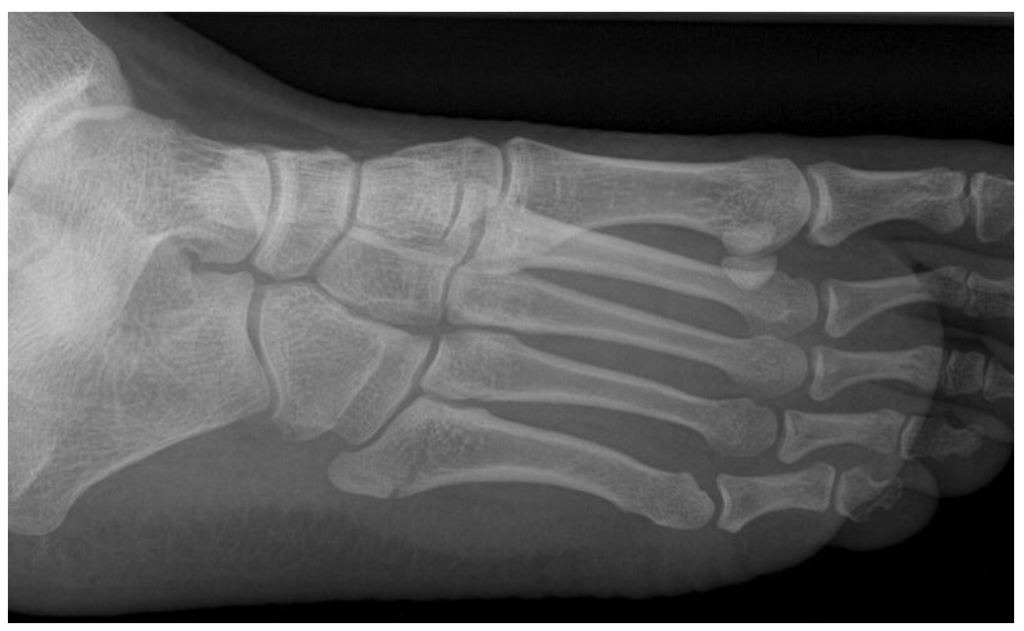

Перелом джонса без смещения 115 фотографий